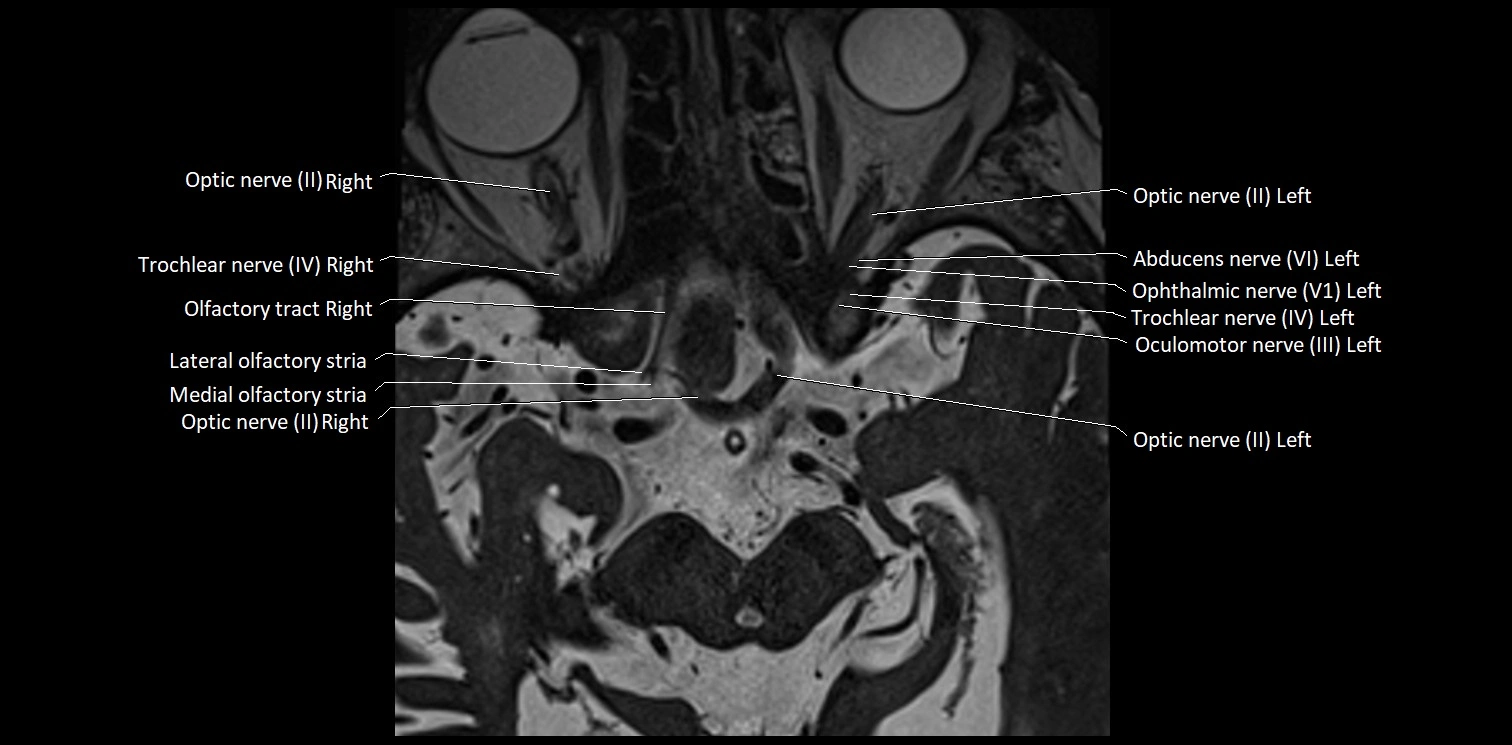

MRI Appearance

• The abducens nerve is a small, thin, linear structure

• Best visualized on high-resolution T2-weighted 3D MRI sequences (e.g., FIESTA or CISS)

• Seen as a hypointense (dark) line running from the brainstem at the pontomedullary junction, traversing the prepontine cistern, and entering Dorello’s canal under the petrosphenoidal ligament, then into the cavernous sinus, and finally the orbit

• May be challenging to visualize in standard MRI due to its small size

• Pathology may be inferred by absence, displacement, or enhancement of the nerve

MRI images

image